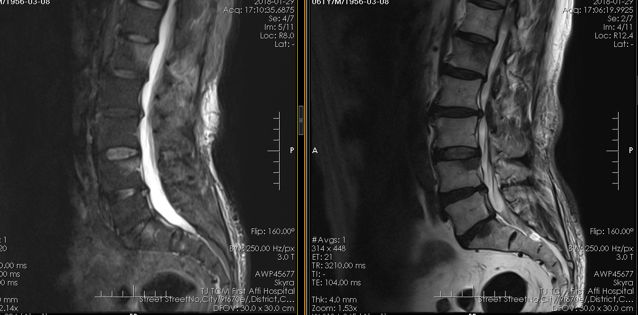

疼痛是大多数骨转移瘤最早出现的症状,>80%,有的转移瘤很小就出现疼痛。乳腺癌如果出现骨疼痛、骨折、碱性磷酸酶升高、高钙血症等可疑骨转移的情况,可以做骨放射性核素扫描(ECT)。MRI、CT和X线检查是骨转移的影像学确诊检查方法。有研究显示,PET/CT具有与ECT相似的灵敏性,更高的特异度,可用于对乳腺癌骨转移治疗后病情的跟踪。如果难以诊断,必要时可以取出一点骨头进行病理检查。